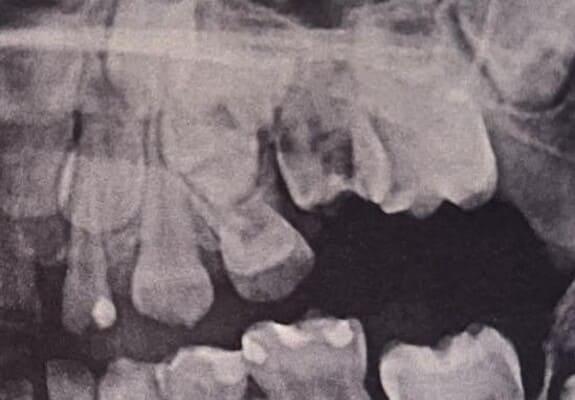

Дівчинка 4,5 років скаржилась на біль в нижньому зубі справа. В зв’язку з високою складністю процедур і значним об’ємом лікування (8 зубів) та після невдалої спроби лікування в звичайному режимі було прийнято рішення про лікування в умовах анестезіологічного забезпечення. Видаленно запалену пульпу (“нерв”) та проведено лікування каналів нижнього зуба ліворуч, цей та сусідні зуби покриті металевими коронками через значний об’єм ураження. Проліковані всі зуби, які потребували допомоги, щоб в майбутньому уникнути болю, дискомфорту та поширення інфекції. Через три години лікування дівчинка може комфортно жувати і не відчувати болю і дискомфорту.